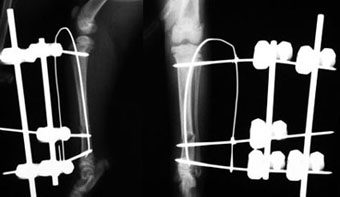

体重1.2kgの猫の脛骨(下腿骨)骨折。

これもピンニングと創外固定をタイインという方法で組み合わせることで、骨折部にメスを入れることなく整復固定しました。

写真上段: 手術前

写真2段目: 手術直後

写真3段目: 手術直後の様子

レーザーでピン刺入部に小さな穴を開けただけで骨折部を開創せず、手術負担が少なかったため、手術直後には着地歩行していました。

写真下段: 抜ピン後